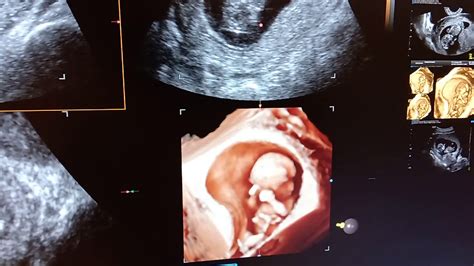

Una dintre cele mai importante modalităţi de a-ţi susţine partenera este să te implici şi să găseşti moduri de a fi conectat cu sarcina. Mergând la consultaţiile prenatale şi la cursurile de educaţie parentală alături de partenera ta, vei obţine informaţiile necesare legate de numeroasele schimbări prin care trec partenera ta şi copilul.

Implicarea partenerului este crucială pentru o sarcină sănătoasă și o relație armonioasă. Alăturarea la consultațiile prenatale și la cursurile de educație parentală oferă informații esențiale despre schimbările prin care trec mama și copilul, consolidând legătura dintre parteneri.